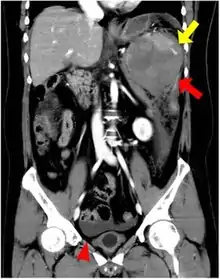

An accessory spleen is a small nodule of splenic tissue found apart from the main body of the spleen. Accessory spleens are found in approximately 10 percent of the population[1] and are typically around 1 centimetre in diameter. They may resemble a lymph node or a small spleen. They form either by the result of developmental anomalies or trauma.[2] They are medically significant in that they may result in interpretation errors in diagnostic imaging[2] or continued symptoms after therapeutic splenectomy.[1] Polysplenia is the presence of multiple accessory spleens rather than one normal spleen.

Accessory spleens may be formed during embryonic development when some of the cells from the developing spleen are deposited along the path from the midline, where the spleen forms, over to its final location on the left side of the abdomen by the 9th–11th ribs. The most common locations for accessory spleens are the hilum of the spleen and adjacent to the tail of the pancreas. They may be found anywhere along the splenic vessels, in the gastrosplenic ligament, the splenorenal ligament, the walls of the stomach or intestines,[3][4] the pancreatic tail,[5][6] the greater omentum,[7][8] the mesentery,[9] the renal fossa,[10][11] or the gonads and their path of descent.[12] The typical size is approximately 1 centimeter, but sizes ranging from a few millimeters up to 2–3 centimeters are not uncommon.[2]

If splenectomy is performed for conditions in which blood cells are sequestered in the spleen, failure to remove accessory spleens may result in the failure of the condition to resolve.[1] During medical imaging, accessory spleens may be confused for enlarged lymph nodes or neoplastic growth in the tail of the pancreas,[5] gastrointestinal tract, adrenal glands or gonads.[2]